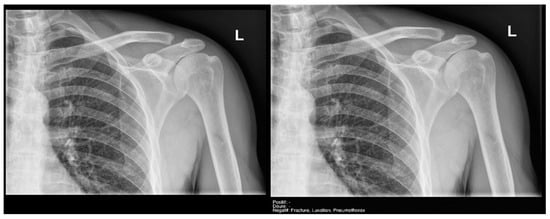

- Ankle and foot: On six occasions, Milvue marked the fracture variable as doubtful in cases with a bipartite medial sesamoid (two patients), an accessory sesamoid at the base of the 5th metatarsal, synphalangism, os peroneum, and os naviculare. (Figure 8).